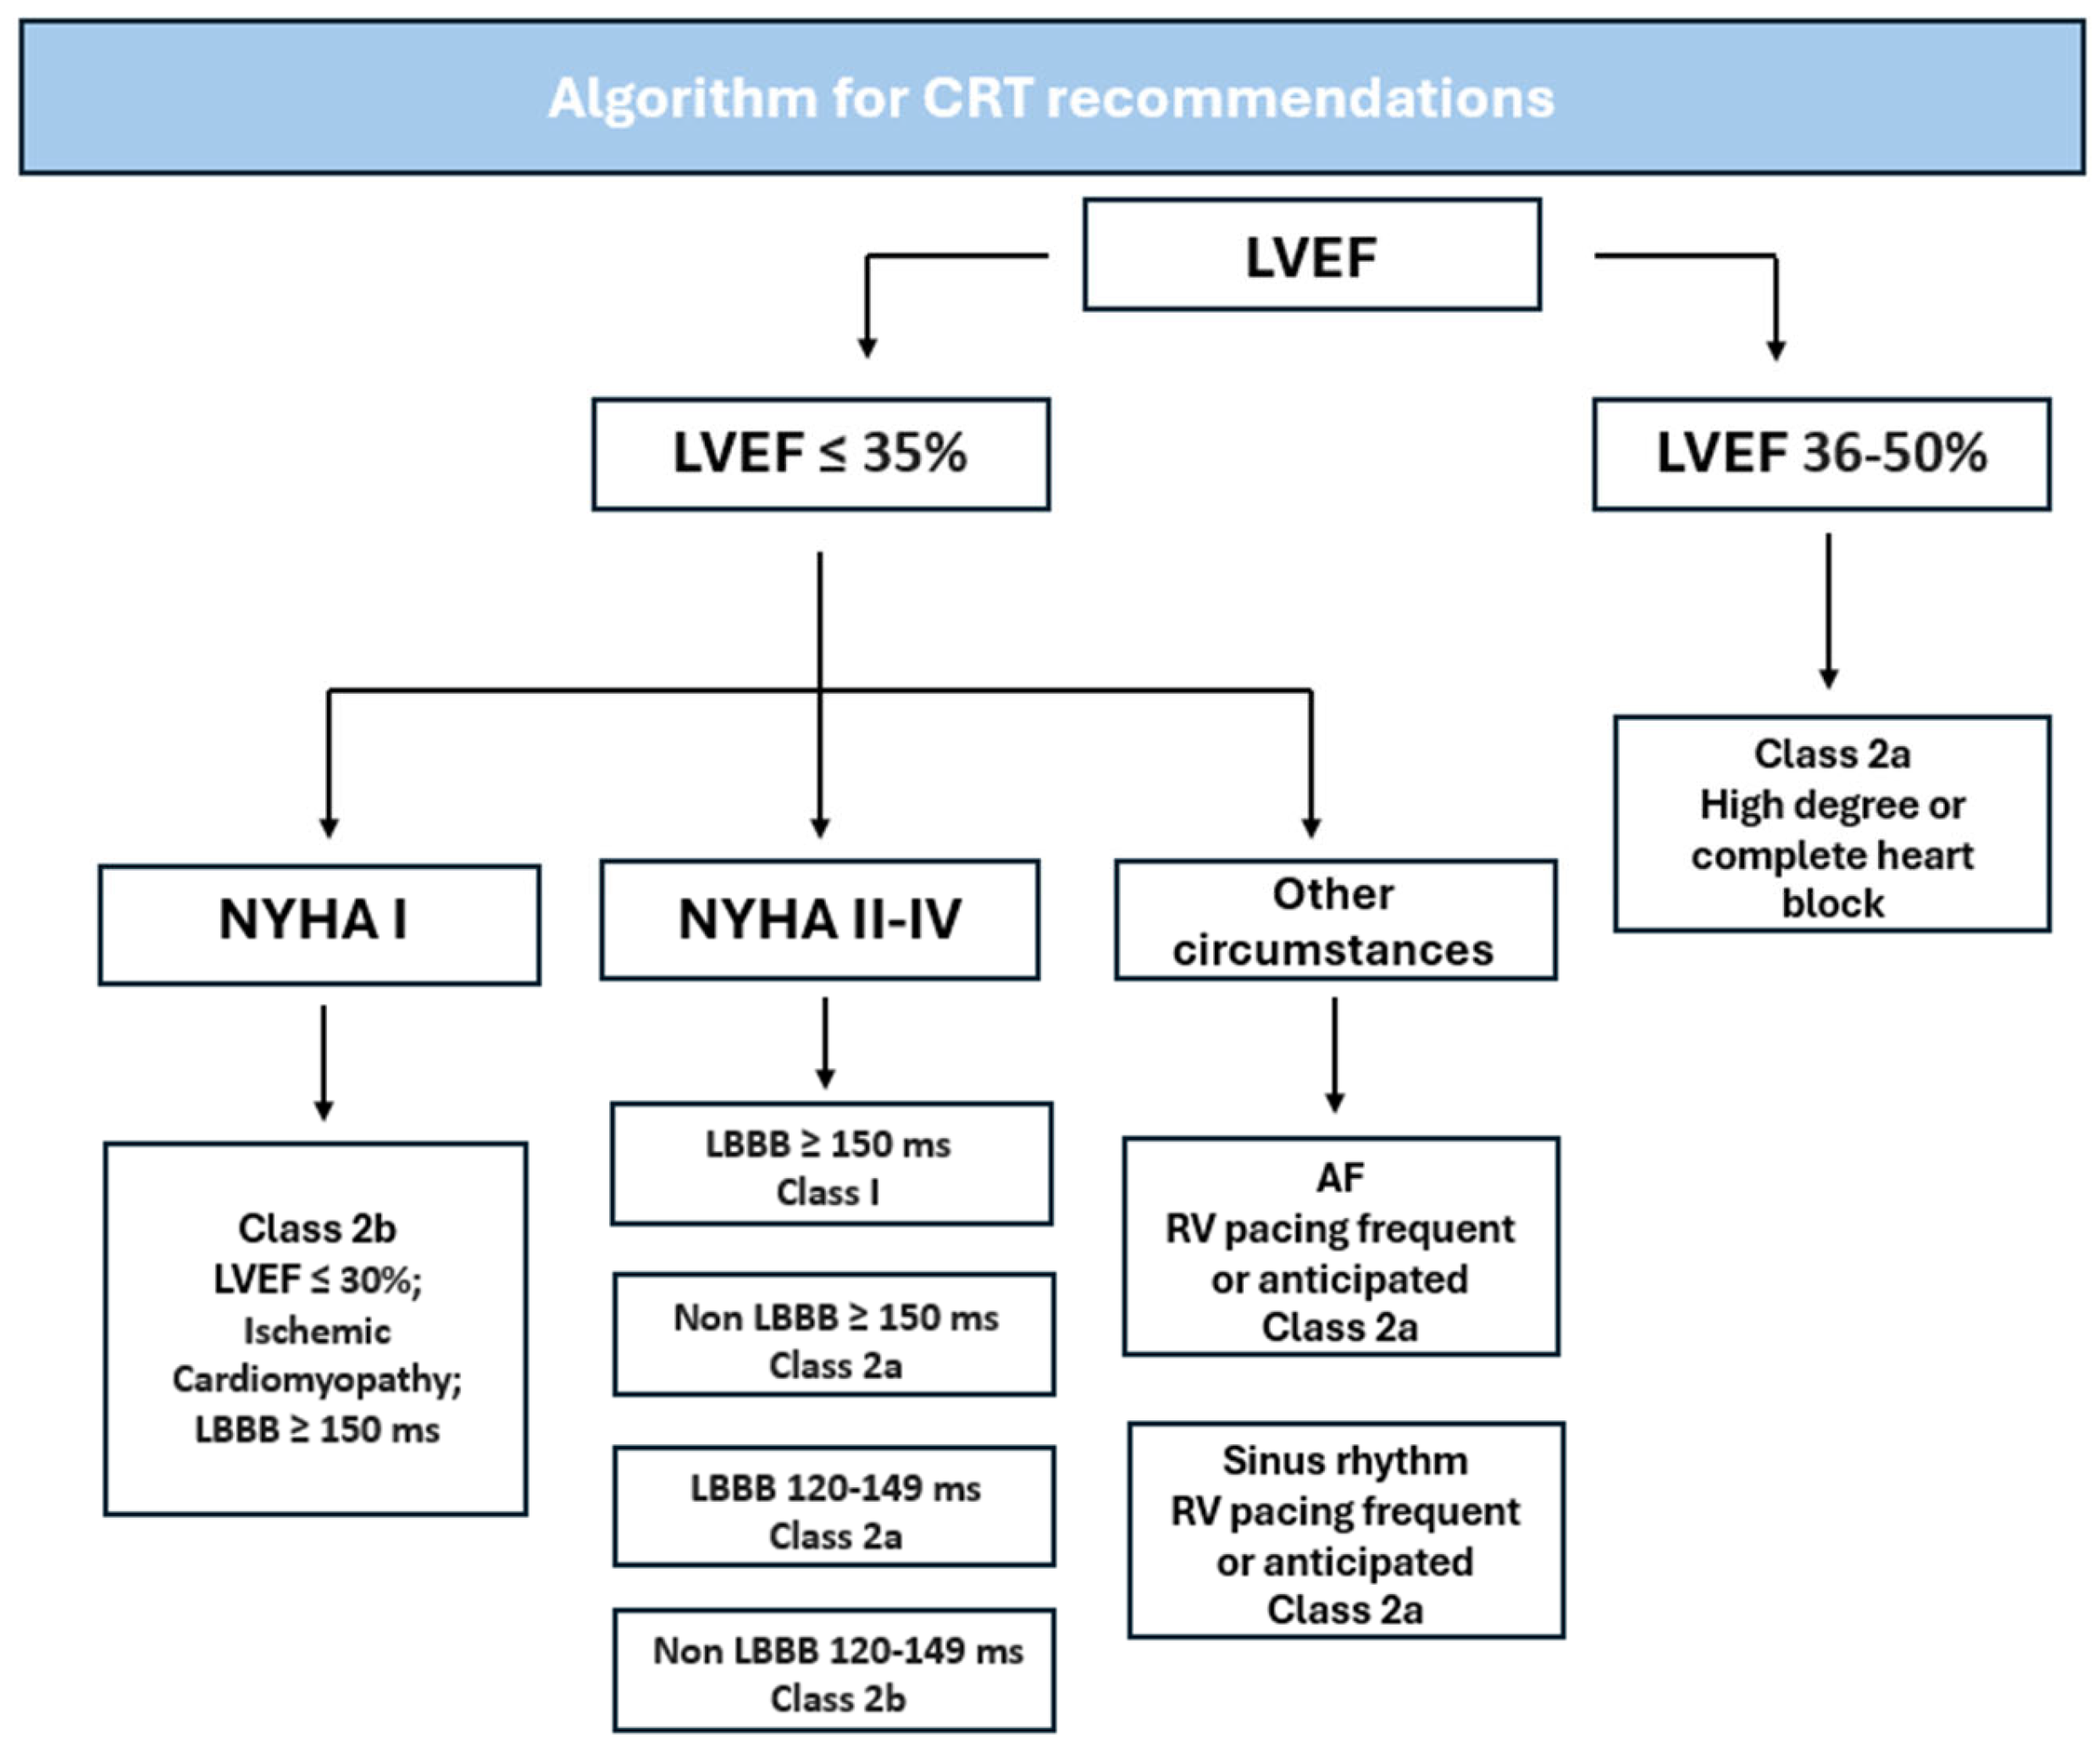

3. Current Guidelines and Recommendations

- Chung, M.K.; Patton, K.K.; Lau, C.P.; Dal Forno, A.R.J.; Al-Khatib, S.M.; Arora, V.; Birgersdotter-Green, U.M.; Cha, Y.M.; Chung, E.H.; Cronin, E.M.; et al. 2023 HRS/APHRS/LAHRS Guideline on Cardiac Physiologic Pacing for the Avoidance and Mitigation of Heart Failure. J Arrhythm. 2023, 39, 681–756. [Google Scholar] [CrossRef] [PubMed]